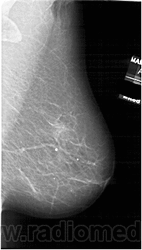

Жирная (не плотная) грудь

Умеренно плотная грудь

Плотная грудь

Маммограммы представляют собой изображения структур, проецируемых на плоскость: плотная грудная маммограмма, следовательно, состоит из многих других структур, которые необходимо проанализировать, чем более жирная, пустая грудь. По этой причине диагностировать рак молочной железы труднее для моложе, чем для пожилых женщин.

Нажмите на миниатюрные картинки, чтобы получить увеличенный размер.